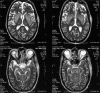

Dyselectrolytemia, especially hyponatremia is a common occurrence in hospitalized patients, and a number of dreaded complications arise out of the disorder itself and its treatment. Osmotic demyelination syndrome develops secondary to rapid correction of hyponatremia. As the disease is rare and available literature from Intensive Care Units are limited, we report our retrospective observation over 5 years. Overall incidence was 2.5% with altered sensorium and hypokalemia as most common symptom and associated factor respectively. Isolated pontine involvement was in 41% and combined pontine, and extra-pontine lesions were found in 23% of cases. All patients received supportive therapy; out of which 2 died and complete neurological recovery was seen in 24% of patients. Our findings suggest that a well organized supportive therapy and multidisciplinary approach is of more concern than many available therapeutic modalities which are still to be proved.